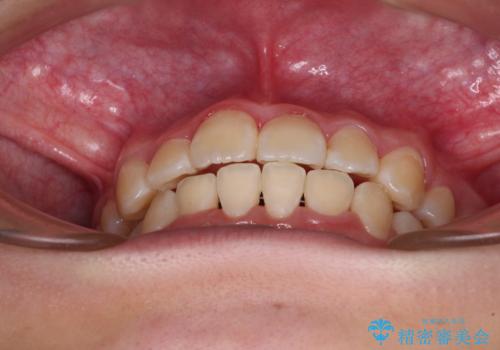

正中位置の改善に時間がかかることが予想され、2年半を治療期間の目標としておりましたが、20歳と年齢が若いこともあり、2年2ヶ月で治療を終えることができました。